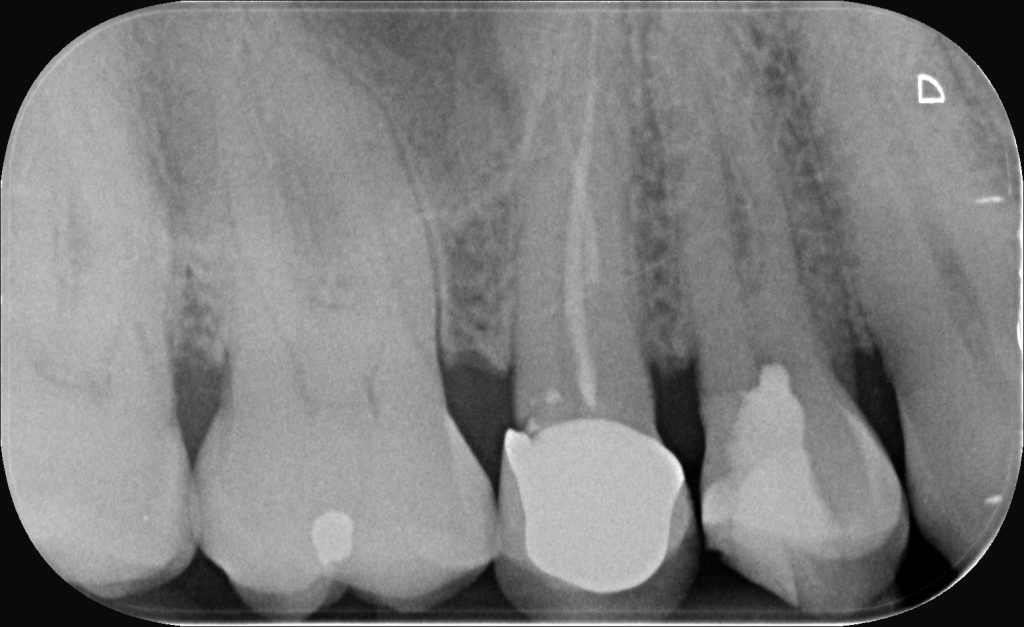

Des séries de cas et rapports cliniques ultérieurs, notamment sur des molaires temporaires et permanentes, ont mis en évidence des taux de succès élevés à moyen et long terme, avec disparition des symptômes, normalisation du ligament alvéolo-dentaire et maintien fonctionnel de la dent.

Dans ce contexte, le cas clinique présenté illustre le protocole de pulpotomie tampon à une prémolaire présentant une pulpite irréversible et une hémorragie persistante.